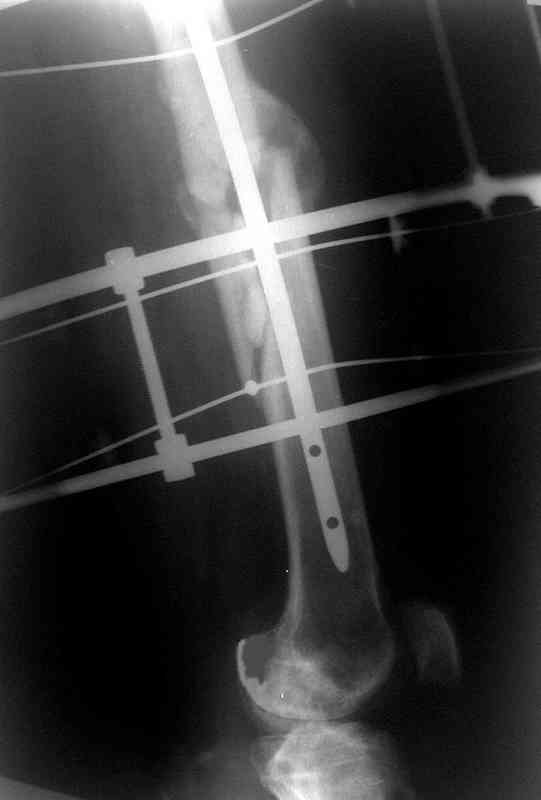

по его наружной поверхности послеоперационный рубец - рана зажила первичным натяжением. При измерении длины бедер обнаружено укорочение левого бедра на 4,5 см. На рентгенограммах этого бедра: ось конечности правильная, отмечается захождение основных костных фрагментов по длине, проксимальный конец штифта выступает слишком медиально и высоко относительно большого вертела, периостальная мозоль незначительна.22.12 - через 6 месяцев после операции, произведенной в ЦРБ, нами по поводу замедленно консолидирующего перелома левой бедренной кости с ее абсолютным укорочением под наркозом произведена операция: удаление штифта, закрытый блокирующий интрамедуллярный остеосинтез перелома левого бедра штифтом без рассверливания (UFN) длиной 40 см, диаметром 10 мм с блокированием только проксимальных отверстий (динамический остеосинтез). Наложен аппарат Илизарова на 4 полукольцах с целью удлинения укороченного бедра. Послеоперационное течение без особенностей. Ежедневно осуществляли дистракцию отломков на 1 мм. Через 3 недели после операции больной выпи-сан на амбулаторное лечение с продолжением дистракции отломков. В течение 1,5

месяцев дистракции укорочение левого бедра удалось полностью устранить. 22.02.00, т.е. через 2 месяца после повторного остеосинтеза, больному произведено дистальное блокирование штифта двумя винтами и демонтирован аппарат Илизарова. В течение 2 недель после операции больной ходил с помощью костылей, потом 2 недели с тростью. Опороспособность и функция оперированной конечности полностью восстановились через 4 недели после операции.

Фиксаторы удалены через 12 месяцев после операции, выполненной по поводу замедленной консолидации перелома бедра с его укорочением.

На финальных снимках видно - сращение прям таки железное. Если Вы не устали отвечать, осмелюсь задать еще вопрос - что-то принимал пациент в целях ускорения сроста (кальций, режим питания). Интересны также вопросы восстановления функций конечности - в какой период были рекомендованы группы упражнений для восстановления основных групп мышц?